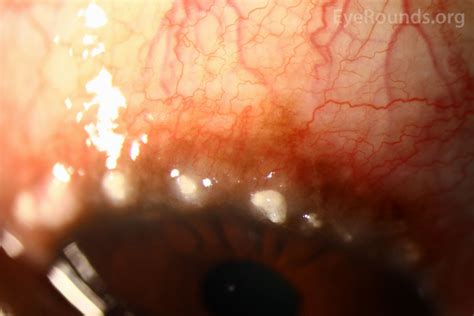

The Eye Limbal area, clinically referred to as the limbus, is the transitional zone between the transparent cornea and the opaque, white sclera. This region is roughly 1.5 to 2 millimeters wide and serves as the primary anchorage point for the conjunctiva. Beyond its physical location, it is a highly vascularized area, providing a crucial blood supply that the central cornea lacks. The most remarkable feature of this zone is its role as a reservoir for Limbal Epithelial Stem Cells (LESCs).

These specialized cells are located in the crypts of the limbus, often referred to as the Palisades of Vogt. These radial, spoke-like structures protect the stem cells from external trauma while ensuring they have a niche to differentiate and migrate. Without the regenerative capabilities provided by this zone, the corneal surface would quickly become compromised, leading to clouding, vascularization, and permanent vision loss.

• Inflammatory Response: Due to its dense vascular network, the limbus serves as the front line for the immune system to respond to pathogens or injuries on the ocular surface.